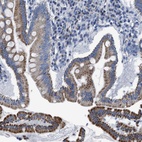

Immunohistochemical staining of human duodenum shows granular cytoplasmic positivity in glandular cells.